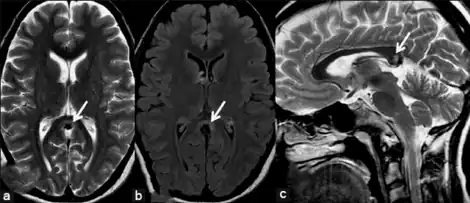

There is no definitive diagnostic test for hemicrania continua. Diagnostic tests such as imaging studies may be ordered to rule out other causes for the headache. When the symptoms of hemicrania continua are present, it's considered "diagnostic" if they respond completely to indomethacin. The efficacy of indomethacin may not be long term for all patients, as can eventually become ineffective.